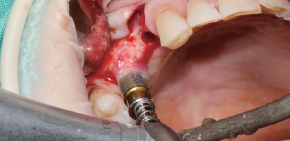

Caso clínico utilizando fresa de obtención Ø3.5/4.0.

by Dr. Soohong Kim, DDS, Ph.D

Se realizó fresado a 300 RPM luego de marcar posición del sitio de implante y obtención.

La pantalla de silicona se llevó a contacto íntimo con los distintos niveles de hueso para prevenir la pérdida de limalla de hueso.

El hueso obtenido se observa con facilidad a través de la pantalla de silicona transparente.

El hueso se transfirió a un frasco luego de desensamblar la pantalla de silicona y stopper.

La cantidad de hueso fue mucho más que la esperada.